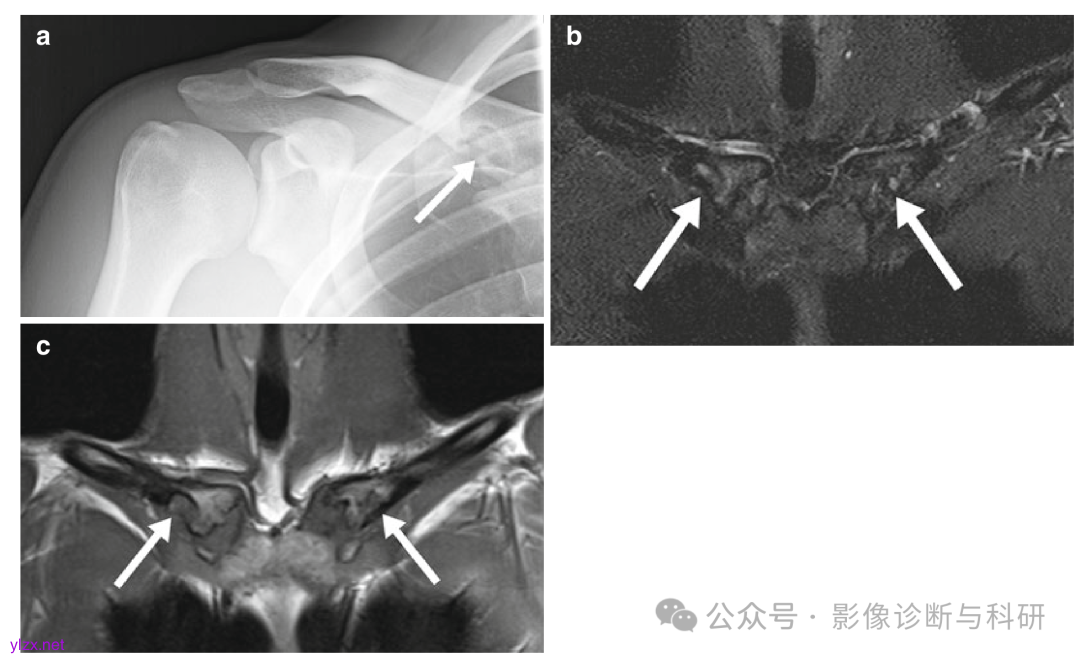

右锁骨菱形窝,19岁,男子,x线提示右锁骨骨质破坏,建议MRI。(a)X线图表显示了一个不规则的溶骨性病变,边缘硬化,累及锁骨内侧面(箭头)。锁骨后关节和锁骨近端的冠状(b)STIR和(c)T1-W MR图像显示锁骨内侧下表面的双侧病变,主要为低信号,与骨组织一致(箭头)。没有相关的软组织肿块。病变在右锁骨稍大。